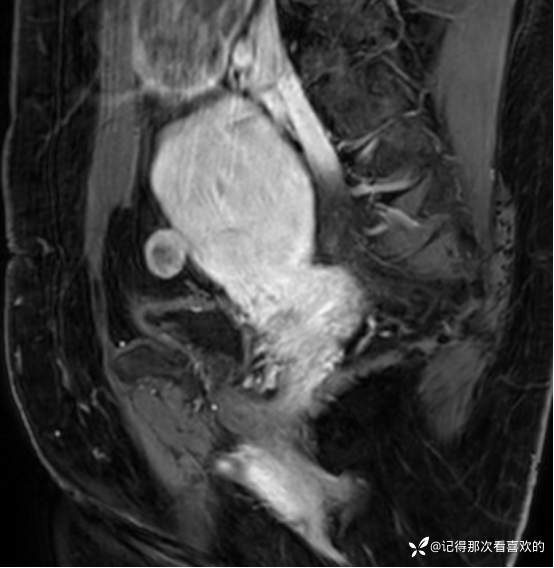

入院后查十二通道常规心电图:1、窦性心律2、逆钟向转位。余相关检验未见明显异常。于2025.05.30在静脉麻醉下行“宫腔镜诊断性刮宫术”,术顺,术后病理(2508387):(宫内容物)子宫内膜息肉。查心脏彩超(Z250530002):三尖瓣轻度反流。双侧下肢深静脉血管彩色多普勒超声(Z250530003):双侧下肢股总静脉反流,考虑双侧下肢深静脉瓣功能不全。经阴道彩超检查(Z250530004):双侧附件区低回声不均团块,考虑MT,建议进一步检查。子宫多发肌瘤。子宫内膜区低回声结节,考虑粘膜下肌瘤可能。宫颈腺体多发囊肿。盆腔MRI增强(MR109286):1.双侧附件区团块状占位,考虑MT,请结合临床。2.子宫肌层内、浆膜下多发肌瘤。3.子宫腔内异常结节灶,粘膜下肌瘤可能。4.盆腔少量积液。5.右侧髂骨内结节灶,性质待定,建议进一步检查。胸部CT(CT384707):1.双肺多发微小结节,建议随诊复查。2.气管憩室。3.扫及右肾结石?新上腹部CT平扫(CT384838):盆腔右侧占位性病变,请结合临床及MRI检查。HPV+TCT:HPV阴性;非典型鳞状上皮细胞(不能明确意义)。2025.06.03行胃肠镜,电子胃十二指肠镜检查(PG25003031):胃体溃疡(待病理);慢性萎缩性胃炎。电子结肠镜检查(PC25002608):结肠多发息肉(内镜下息肉切除+钳除)。快速石蜡病理(2508504):胃体:低分化腺癌,伴少量印戒细胞癌成分,免疫组化结果待补充报告。快速石蜡病理(2508505):降结肠:增生性息肉。